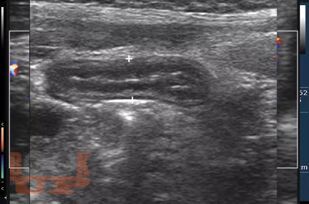

Лучевые методы исследования в диагностике острой хирургической патологии органов брюшной полости

В учебном пособии представлены наиболее часто встречающие острые хирургические заболевания органов брюшной полости. Представлены возможности современных методов лучевого исследования в диагностике острой хирургической патологии органов брюшной полости, а также вопросы клинической диагностики. Пособие предназначено для клинических ординаторов, хирургов, для врачей лучевой диагностики, а так же для врачей других специальностей.